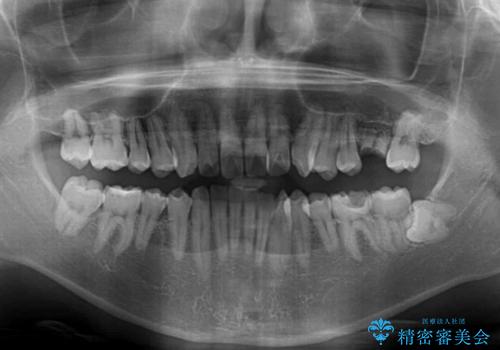

- 前歯のクロスバイトと、大学生のころから放置している虫歯を気にして来院された患者様です。

マウスピースでの矯正治療を希望されていましたが、前歯のクロスバイトは不十分な仕上がりや歯髄壊死などのリスクが高くなるため、術前にワイヤーで大まかに整えてからインビザラインにて矯正治療を行うこととしました。

奥歯の虫歯は抜歯が必要であったので、矯正治療前に抜歯をし、矯正治療と並行してインプラントによる補綴治療を行うこととしました。